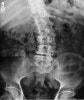

선 자세에서 전체 척추 AP, lateral view 검사를 합니다.

X-ray : 성인의 측만증(Scoliosis in adults)